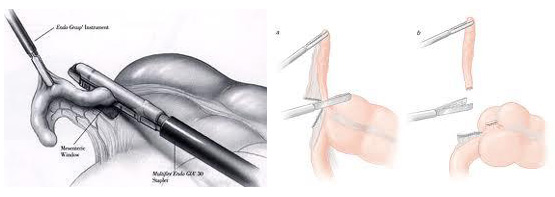

Χρησιμοποιώντας ένα σκληρό πλαστικό καθετήρα (trocar), ο χειρουργός εισέρχεται στην κοιλιά δημιουργώντας πνευμοπεριτόναιο. Έπειτα ένα λαπαροσκόπιο, (μικροσκοπικό τηλεσκόπιο συνδεδεμένο με μία βιντεοκάμερα) εισάγεται μέσω του trocar , δίνοντας στο χειρουργό μία μεγεθυμένη εικόνα των εσωτερικών οργάνων του ασθενούς σε μια οθόνη τηλεόρασης. Μέσω άλλων trocars ο χειρουργός χειρουργεί και αφαιρεί την φλεγμονώδη σκωληκοειδή απόφυση. Η όλη διαδικασία μπορεί να ολοκληρωθεί μέσα από τα trocars ή με επιμήκυνση σε μία από τις μικρές τομές για την είσοδο των trocars.